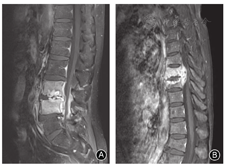

椎间盘脓肿形成强烈提示化脓性脊柱炎,MR增强扫描可见椎间盘周围的强化表现[16](图6)。64%的化脓性脊柱炎患者出现上述表现,而结核患者比例为9%[9]。椎体内脓肿形成并出现周围强化提示为脊柱结核,文献报道79%结核患者出现椎体内脓肿,而化脓性脊柱炎几乎为零[9]。结核和化脓性炎症均可导致椎旁脓肿和硬膜外脓肿,但发生率存在争议。Kim等[7]认为结核和化脓性炎症出现脓肿的比例类似;而Chang等[9]认为结核比化脓性炎症更容易出现椎旁脓肿(82% vs. 30%)和硬膜外脓肿(91% vs. 62%)。我们认为结核患者出现上述两个部位脓肿的比例更高,脓肿体积更大,可跨越病椎向上、下延伸。此外,我们还发现结核形成的脓肿经MR增强扫描,显示脓肿壁光滑且很薄;而化脓性炎症的脓肿壁往往较厚且边界不清(图7)。此与文献报道相一致[15,17]。

MR增强扫描显示椎体强化的信号表现对于鉴别诊断亦有帮助。由于结核患者椎体内部广泛死骨和脓肿形成,因此出现局灶性、混杂性强化信号;而化脓性炎症患者的椎体破坏往往局限在椎间盘周围,椎体表现为炎性反应,故增强扫描表现为均一弥散的炎症性水肿强化信号[18,19](图6)。